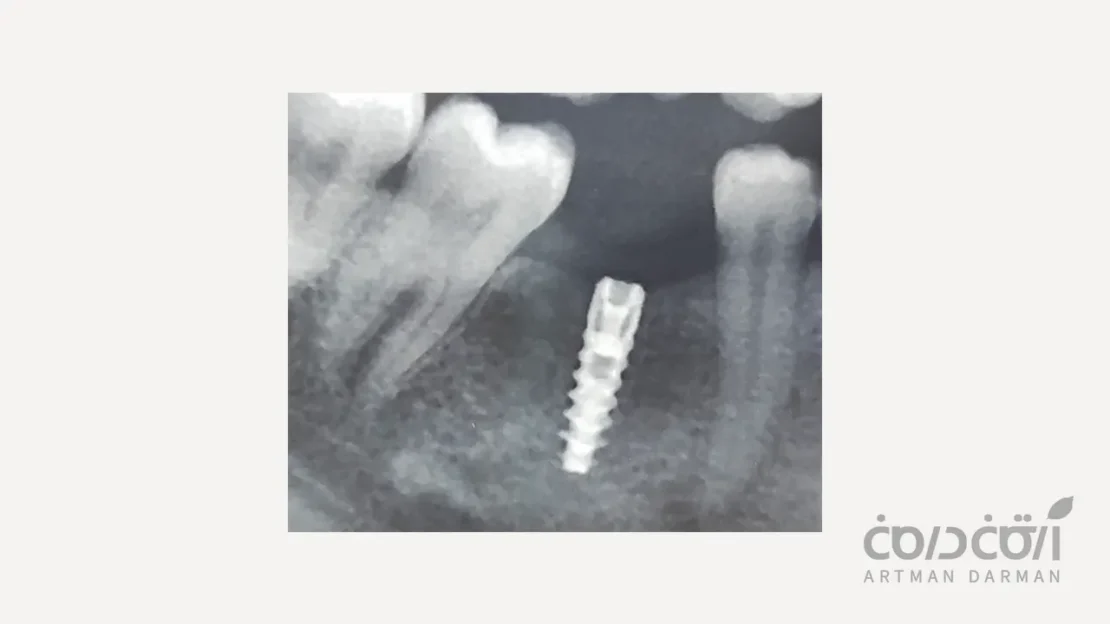

این نوع شکست در چند هفته یا چند ماه اول پس از جراحی، یعنی قبل از تحویل روکش نهایی و در حین فرآیند جوش خوردن به استخوان، رخ می دهد. در این حالت، فرآیند اوسئواینتگریشن به درستی اتفاق نمی افتد.

کیفیت و کمیت ناکافی استخوان

این یکی از دلایل اصلی است. تلاش برای قرار دادن ایمپلنت در استخوانی که بیش از حد نرم (کیفیت پایین) یا کم حجم (کمیت ناکافی) است، بدون انجام پیوند استخوان مناسب، می تواند منجر به عدم دستیابی به ثبات اولیه و شکست شود.